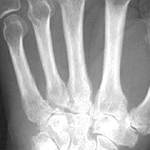

Hands Up

artist: death